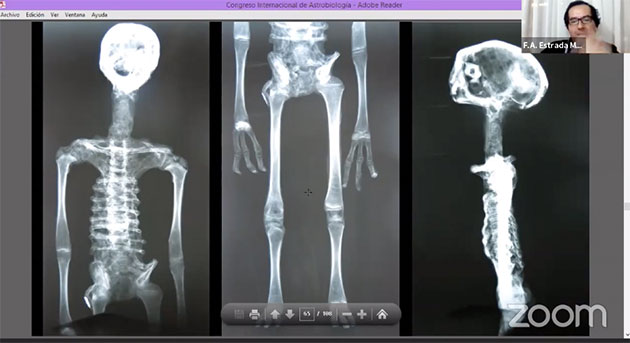

Zu „Material und Methoden“ erläutert Estrada Moreno, dass hierzu Röntgenaufnahmen der besagten Mumien, ebenso wie Aspekte der vergleichenden Anatomie und Analysen mit Infrarot-Spektroskopie zum Einsatz kamen, mit der die Zusammensetzung von Material und Stoffen zerstörungsfrei und von außen durchgeführt werden kann.

Anhand der Röntgenaufnahme (Abb. 36) ist zu erkennen, dass dieses Wesen überhaupt keine Halswirbel oder sonstige Halsknochen besitzt. Zugleich gibt es aber auch keine Anzeichen für eine diesen Hals und damit den Kopf stützende Muskulatur. Eine weitere anatomische Katastrophe ist der Einbau der Oberschenkel, die wie Arme platziert wurden. Zudem verfügt das Wesen über keine wirklichen Gelenke. Mit Ausnahme des Schädels stammen auch hier alle Knochen von Menschen – in diesem Fall von noch nicht ausgewachsenen Menschen, da sich an den Knochen Wachstumslinien erkennen lassen. Anhand dieser Merkmale schließen die Wissenschaftler, dass der Mensch, dessen Knochen hier verwendet/missbraucht wurden, Ernährungsprobleme hatte.

Albertos Schädel (Abb. 37 l. weiß) ist ähnlich gearbeitet, wie die vorigen Schädel der anderen kleinen Mumien (Abb. 37. r. blau), besteht selbst aber fast ausschließlich aus einem sogenannten Gehirnschädel (Neurokranium), der das Gehirn umschließt. Es finden sich keine weiteren Schädelteile. Die Röntgenaufnahmen (37) zeigt das anschaulich. Erneut vermuten die UNICA-Wissenschaftler, dass die weiße pudrige Farbe auf den Mumien oberflächlich offenkundige Fehler verdecken sollte.

Auch die Machart von Albertos dreifingrigen Händen (Abb. 38), entspricht der voriger Proben (Abb. 29, 30).

Die Frau, deren Körper als Ausgang für die modernen Präparation darstellt, besaß einen mechanisch herbeigeführten sogenannten Langschädel (…GreWi berichtete). Die UNICA-Archäologen gehen davon aus, dass „Maria“ ursprünglich in ihrer Position bestattet wurde, da es sich um die klassische Körperhaltung prä-spanischer Bestattungen handelt, in der die Arme vor oder auf den angewinkelten Beinen verschränkt und teilweise zum Erhalt der Position in Textilien eingewickelt wurde. Eine Analyse der Knochen und Körpergröße zeigt, dass Maria zum Zeitpunkt ihres einstigen Todes bereits ausgewachsen war.

Schon das Röntgenbild (Abb. 52) zeigt, dass Marias Schädel samt Zähnen eindeutig menschlich ist. Auch das sonstige Skelett und die Anatomie sind eindeutig menschlich, wie dies aus weiteren Scans (MRT usw.) hervorgeht. Hier zeigt sich auch, dass die auf den ersten Blick ungewöhnlich großen Augen lediglich auf die normal großen Augenhöhlen zurückgehen – ein Effekt, der von vielen Mumien unterschiedlicher Kulturen (Abb. 55-57) bekannt ist.

Ab Timecode 1.06:12 geht Moreno nochmals auch die Röntgenanalysen einiger Mumien ein und zeigt, wie sich die unterschiedlichen Materialien (Aire = Luft, Grasa = Fett, Agua = Wasser, Hueso = Knochen und Metall, s. Abb. 64) in der Röntgenbetrachtung abbilden.